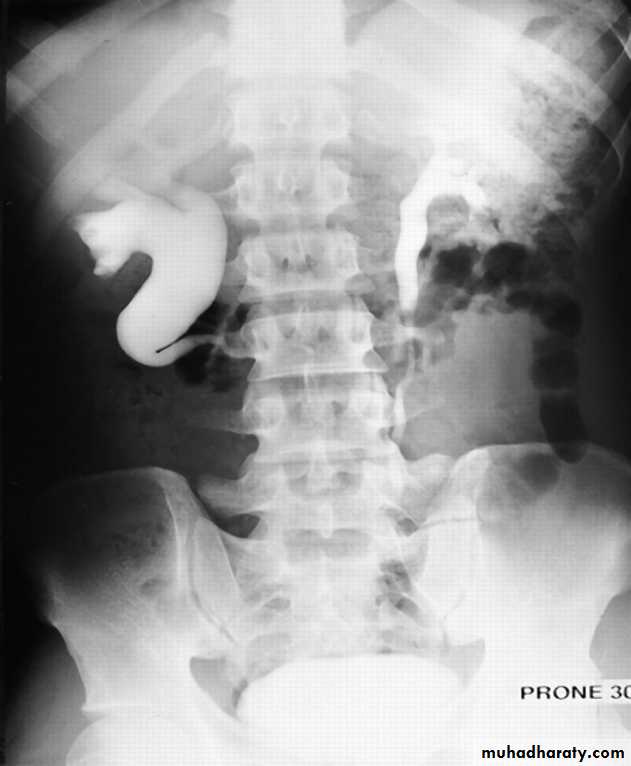

IVU

Large kidney .

Lobulated out-line.

Distortion of pelvi- calyceal system depend on cyst size, number and position.

In advanced cases there is elongation and stretching of minor and major calyces ( spider leg).

In advanced cases IVU shows non-functioning kidney .